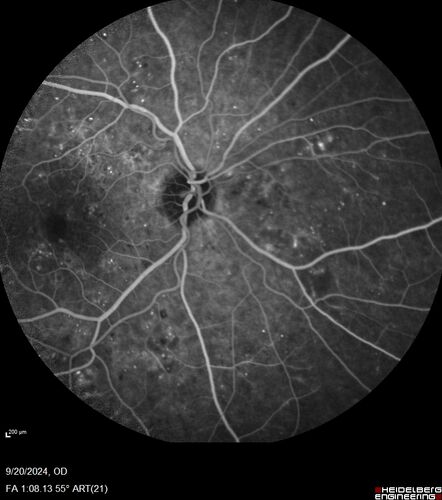

Severe NPDR

53 year old man with blurred vision (needs glasses).

Diabetic for 10 years with poor control

VA 20/32 OU